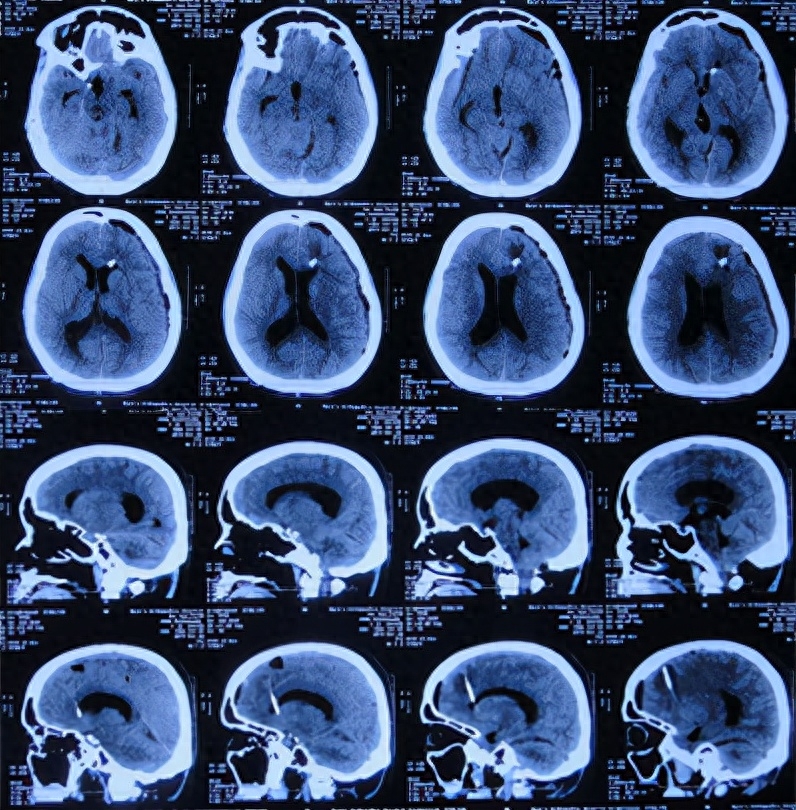

入院治疗48天即2019年5月15日,进行了右侧脑室-腹腔分流术(图-17)。

图-17:2019年5月15日头颅CT

入院治疗58天即2019年5月25日,康复出院。出院时:神清气爽,身体完全正常(图-18)。

图-18:2019年5月25日出院时